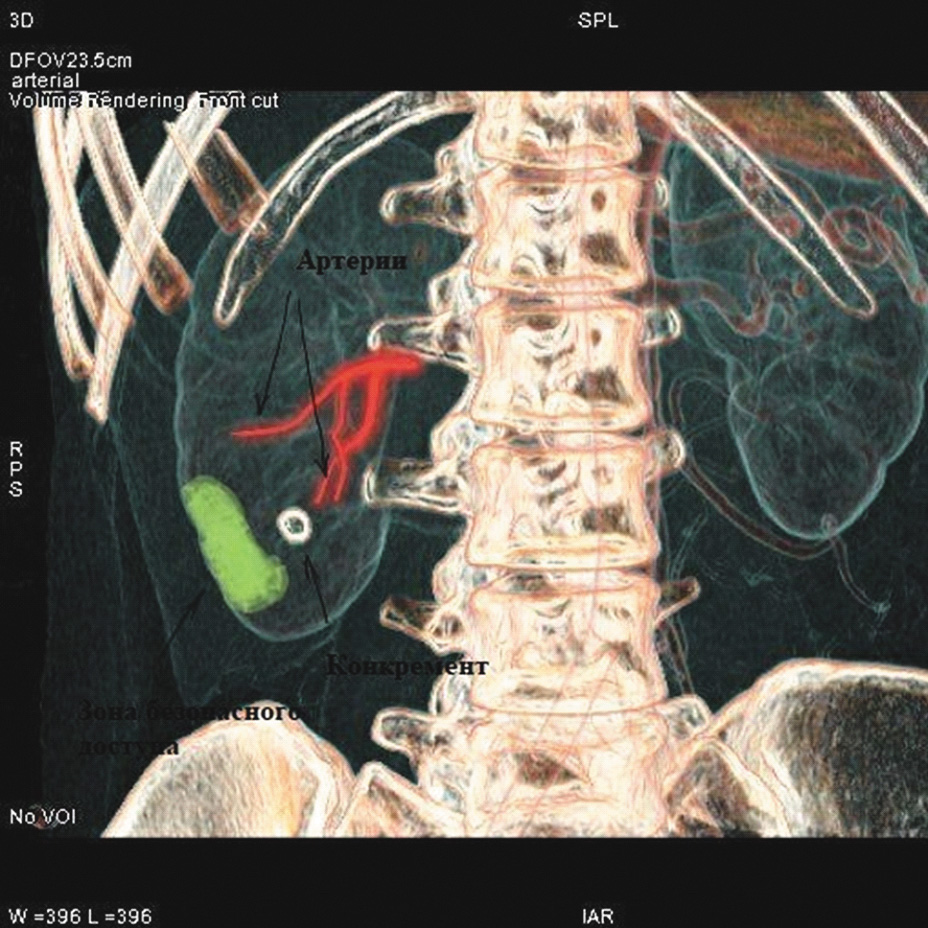

Нами были изучены результаты 60 мини-перкутанных литотрипсий. Все они проводились с использованием 3D-планирования доступа в программах «Автоплан», «Луч-С» и VessellQ Xpress. При нативном и отсроченном сканировании находили целевую группу чашечек, содержащую конкремент. В артериальную фазу определяли тип кровоснабжения почки и ее малососудистые зоны (рисунки 1, 2).

Рисунок 1. Определение строения артериального русла почки (артерии выделены дополнительно).

Рисунок 2. Определение малососудистой зоны (артерии выделены дополнительно).

После определения линейных размеров и сосудистой анатомии почки с выявлением малососудистых зон осуществлялось планирование точки и траектории доступа с нанесением на кожу визуальных маркеров для последующей интраоперационной оценки точки пункции и направления движения пункционной иглы (рисунок 3).

Рисунок 3. Планирование трассы чрескожного доступа.